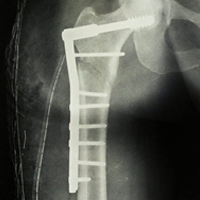

Case:7 Fracture Neck Femur with Implant failure and Re-Fixation with hemi-arthroplasty

Alcoholic Gardener by profession had slipped in bathroom & fell. He sustained fracture neck femur.He was operated with closed reduction & CC Screw fixation under IITV. Two weeks’ post fixation he again fell & sustained fracture in sub trochanteric region. He was treated with Hem-Arthroplasty with Tension band wiring.

Pre-Op

Post-Op

Post Fall

Post Uninon-3Months